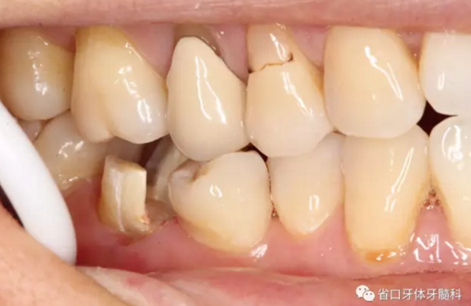

圖3 牙體預備后,近中頰側(cè)牙體缺損平齊齦緣;近頰根管口流動樹脂覆蓋牙膠不足,下次改進